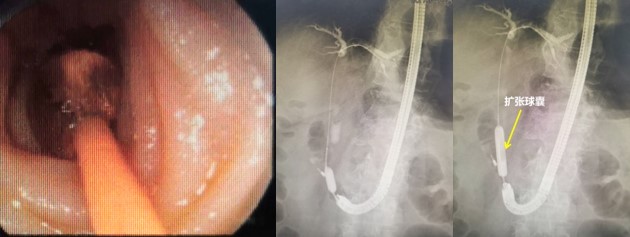

赵刚副主任凭借丰富的经验和精湛的技术,运用胃镜佩戴透明帽顺利找到前期设定的钛夹标记及十二指肠主乳头,然后利用专业器械,在内镜精细操作下,成功进行乳头括约肌切开及球囊扩张术,并最终将胆管内结石顺利取出。整个操作用时不到20分钟。